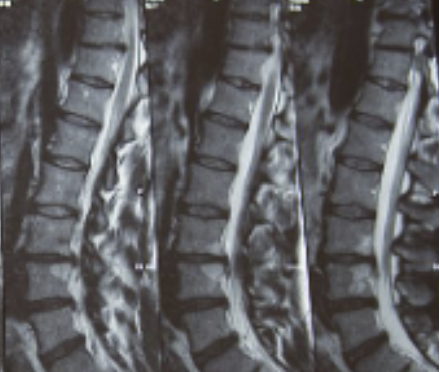

허리디스크를 정확하게 진단하기 위해서는 엑스레이로는 힘들며, MRI를 통해 검사해야 정확하게 볼 수 있습니다.

MRI가 몸에 좋지 않지만 허리 통증으로 엑스레이만 진행할 경우 오진이 많아 지속적인 통증이 계속된다면 허리디스크를 의심하고 MRI 검사를 한번 받아보시길 권유드립니다.